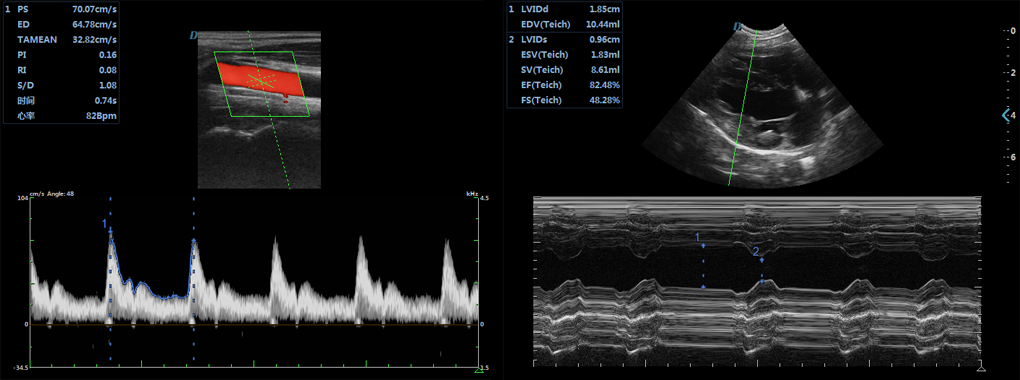

大为动物医疗双屏推车式宠物彩超机采用双屏设计,显示屏和触摸屏可调整位置,让宠物医师在操作和使用时更有趣,多种倒出图像格式,动态图像,静态图像直接以PC格式导出,无需特殊软件,您就可以直接在普通电脑上查看图像,在导出和备份图像数据时,可以执行实时检查,而不会影响检查操作。实时三同步成像(二维、彩色、频谱实时同步成像)模式,满足在操作使用时的功能需求。